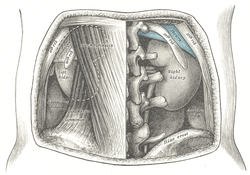

Overview of Ilium as largest bone of the pelvis.

The crest of the ilium (or iliac crest) is the superior border of the wing of ilium and the superolateral margin of the greater pelvis.